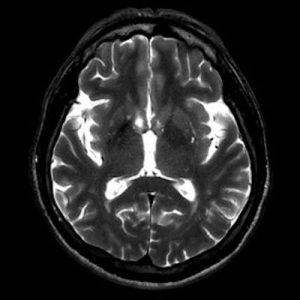

📣📣📣Haftanın ödüllü olgu sorusu yayınlandı.

Yanıtlarınızı www.tnrd.org.tr adresinden bekliyoruz.